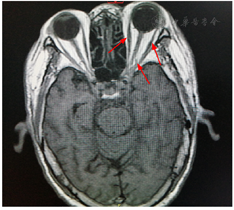

横断面平扫T2 FLAIR序列显示左侧内外直肌及视神经较对侧稍肿胀,其内不均匀信号(箭头所示),代表炎症性改变

The T2 FLAIR sequence of a cross-section plane scan shows that the left rectus muscle and optic nerve are slightly swollen compared to the contralateral side, and the internal uneven signal (arrow) indicates inflammatory changes.

本例患者有带状疱疹感染病史;眼部检查出现视力障碍及眼眶神经不同程度的麻痹如上睑下垂、眼球各方向运动障碍、瞳孔散大;眼眶+视神经磁共振提示左侧内外直肌及视神经较对侧稍肿胀,其内可见高信号影;患者角膜内皮炎和前房炎症反应及视神经病变,导致视力下降。由此一系列疾病演变过程无法用单一神经受损解释,患者无外伤史,眼眶磁共振未见肿瘤,考虑患者可能为眼部疱疹病毒感染未及时就诊,使病毒侵犯神经,最后发展为眶尖综合征。